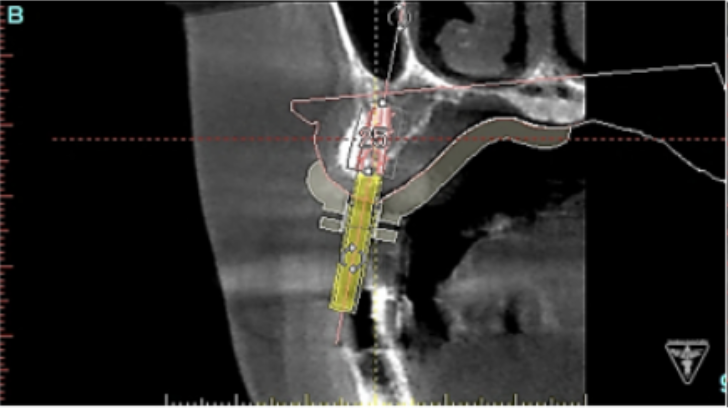

サージカルガイドの作成